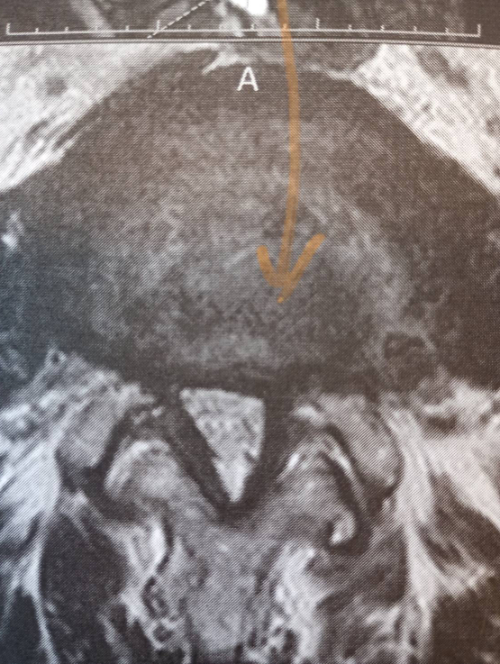

白く映っている部分が脊髄神経で数か所狭くなっている箇所が見られます。変形狭窄とヘルニアによる脊髄神経(もしくは位置的には馬尾神経)圧迫があります。

神経の圧迫があると画像では判断します。(臨床症状と一致)